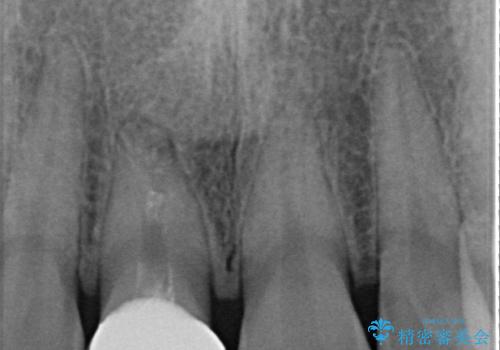

色、形ともに自然で嬉しいですと笑顔で言っていただけました。